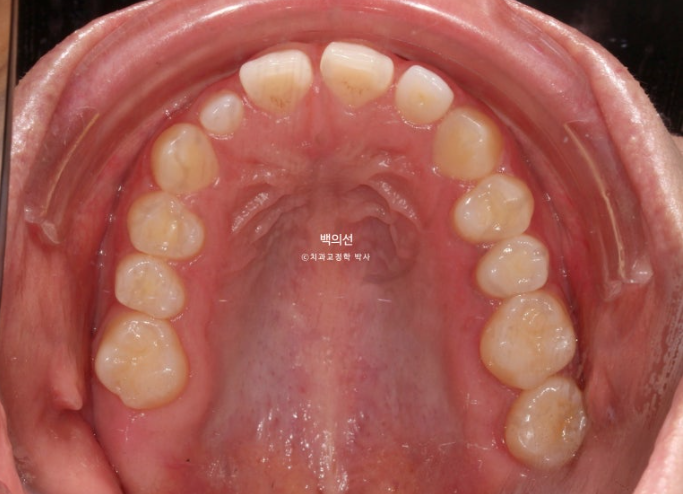

교합면에서 보면 안쪽 맨 뒤 큰어금니 하나가 없는 것이 보입니다.

선천적 결손치아 입니다.

어금니 교합은 물샐틈 없이 좋습니다.

어금니 교합관계는 좌우 모두 1급 입니다.